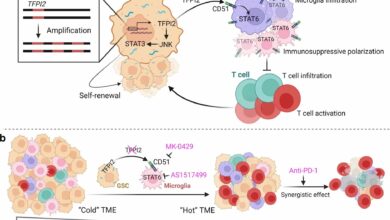

Gene ligado à auto-renovação e imunossupressão de células-tronco de glioblastoma

Modelo de trabalho. a, a ilustração mostra um mecanismo proposto para o TFPI2 e seu eixo de sinalização associado na…